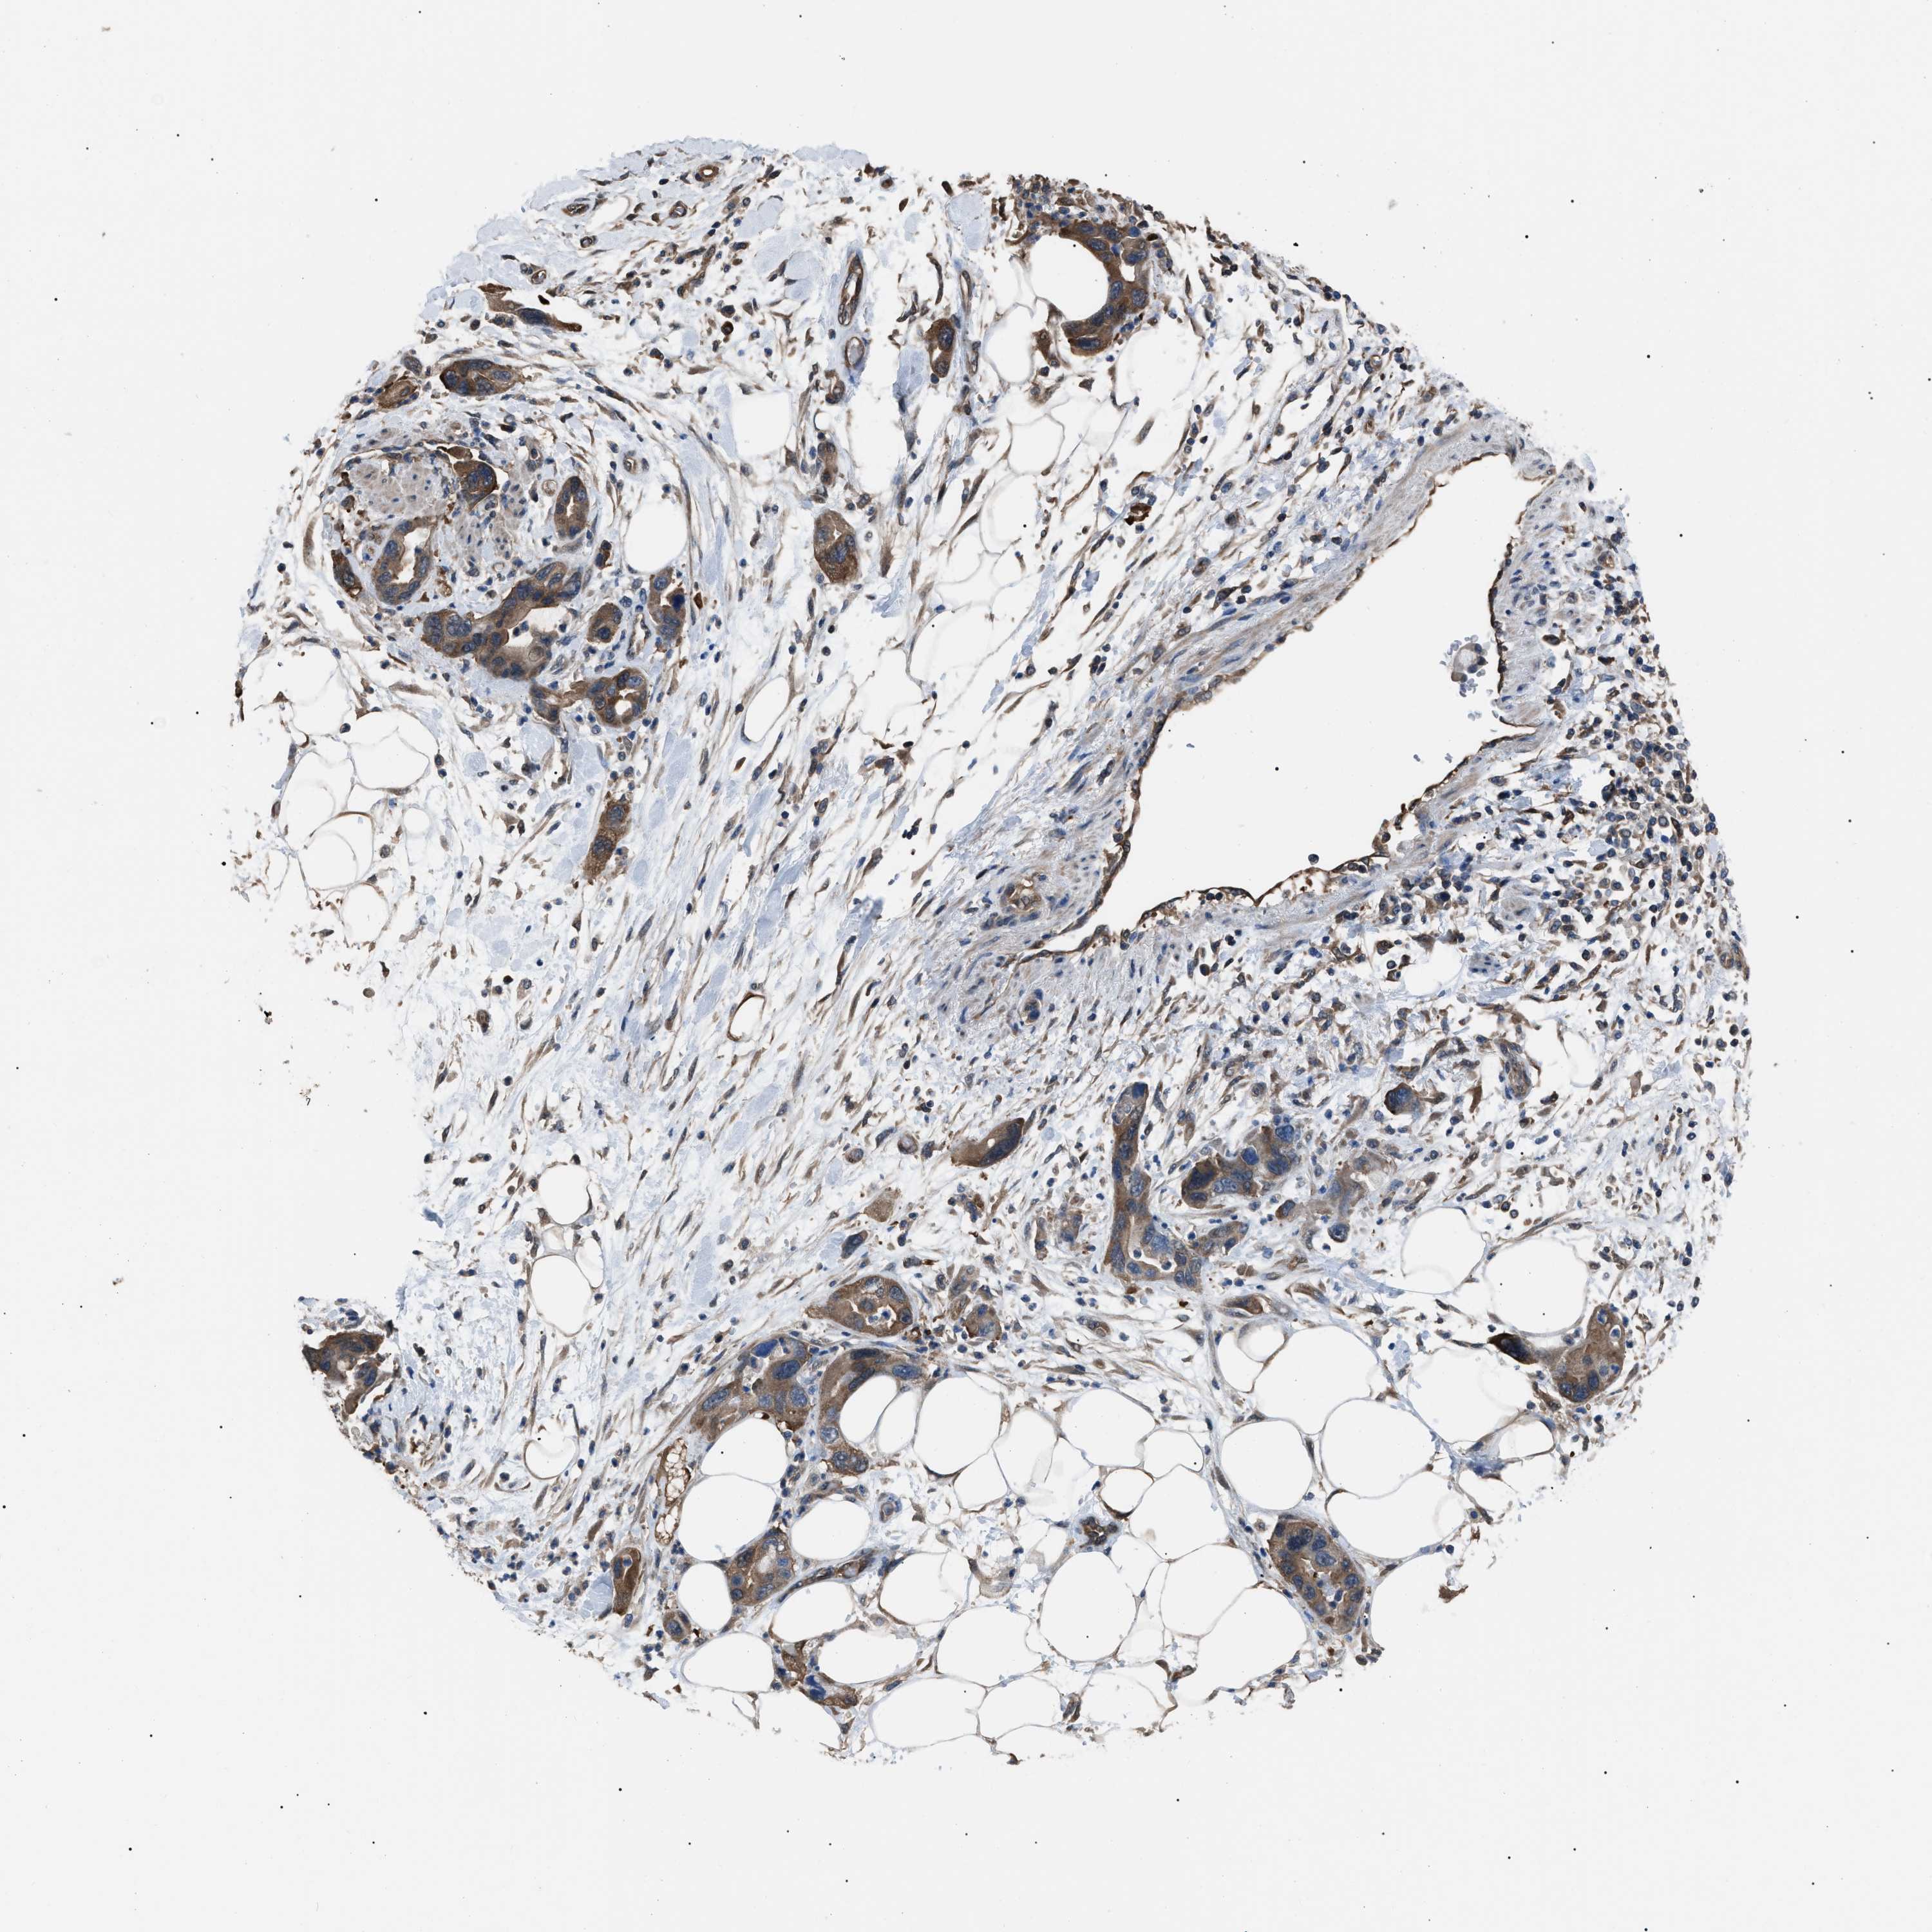

PANCREATIC CANCER - Protein expressioni

A mouse-over function shows sample information and annotation data. Click on an image to view it in a full screen mode. Samples can be filtered based on level of antibody staining by selecting one or several of the following categories: high, medium, low and not detected. The assay and annotation is described here.

Note that samples used for immunohistochemistry by the Human Protein Atlas do not correspond to samples in the TCGA dataset.

Antibody stainingi

Antibody staining in the annotated cell types in the current human tissue is reported as not detected, low, medium, or high, based on conventional immunohistochemistry profiling in selected tissues. This score is based on the combination of the staining intensity and fraction of stained cells.

Each image is clickable and will lead to virtual microscopy that enables deeper exploration of all samples and also displays staining intensity scores, fraction scores and subcellular localization as well as patient and tissue information for each sample.

Antibody HPA018471

Staining

High

Medium

Low

Not detected

Intensity

Strong

Moderate

Weak

Negative

Quantity

>75%

75%-25%

<25%

None

Location

Nuclear

Cytoplasmic/membranous

Cytoplasmic/membranous,nuclear

Adenocarcinoma, NOS